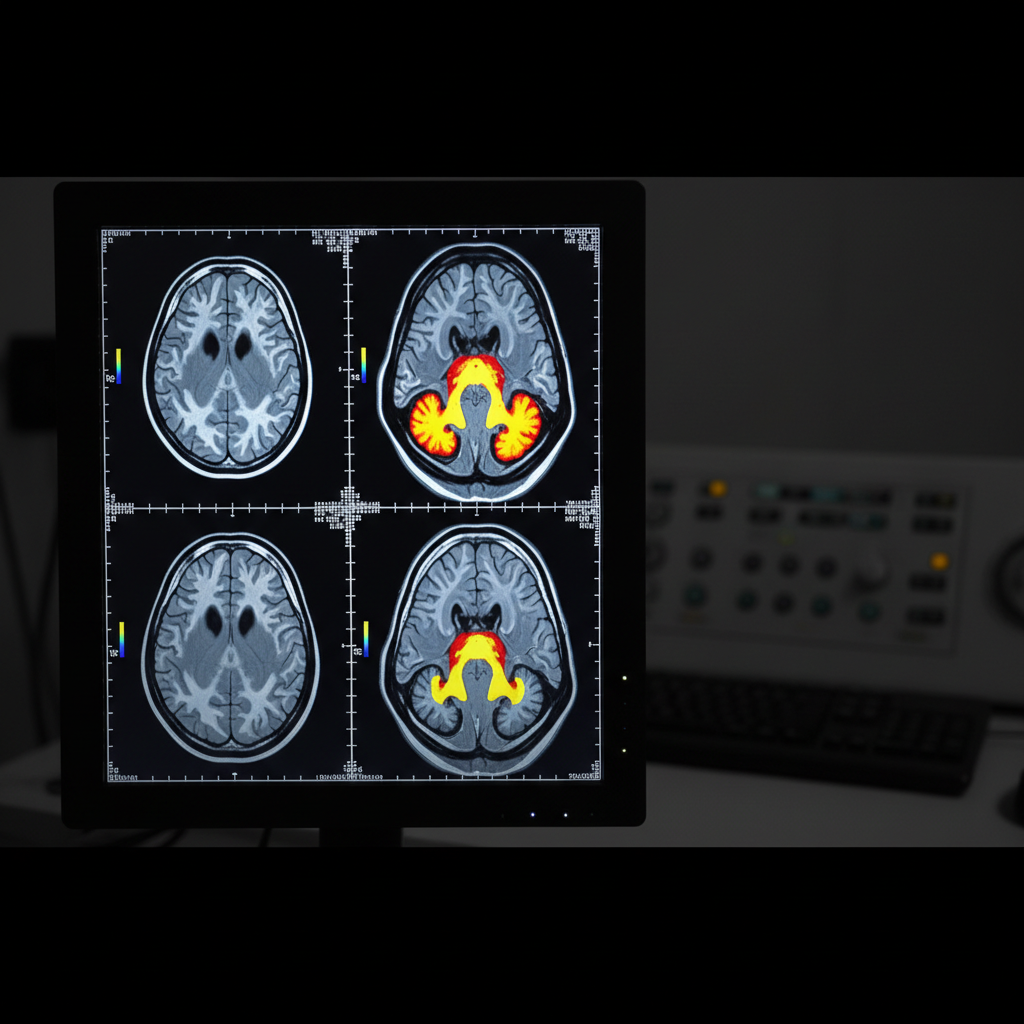

Trauma działa jak wirus w systemie operacyjnym mózgu – niszczy ścieżki neuronalne, blokuje dostęp do wspomnień i prowadzi do powstawania tzw. „czarnych dziur pamięciowych”. Najnowsze badania neuroobrazowe pokazują, że osoby po przeżyciu ciężkiego stresu lub traumy mają zmniejszoną objętość hipokampa – obszaru odpowiedzialnego za konsolidację pamięci (Bremner, 2023). Efekt? Trudności w zapamiętywaniu nowych informacji, déjà vu, nieoczekiwane luki w pamięci, a czasem całkowita amnezja dotycząca traumatycznych wydarzeń.

Równocześnie neuroplastyczność mózgu daje nadzieję – odpowiednia psychoterapia, zwłaszcza EMDR i terapia poznawcza, potrafią przywracać zaburzone funkcje poprzez tworzenie nowych ścieżek neuronalnych.